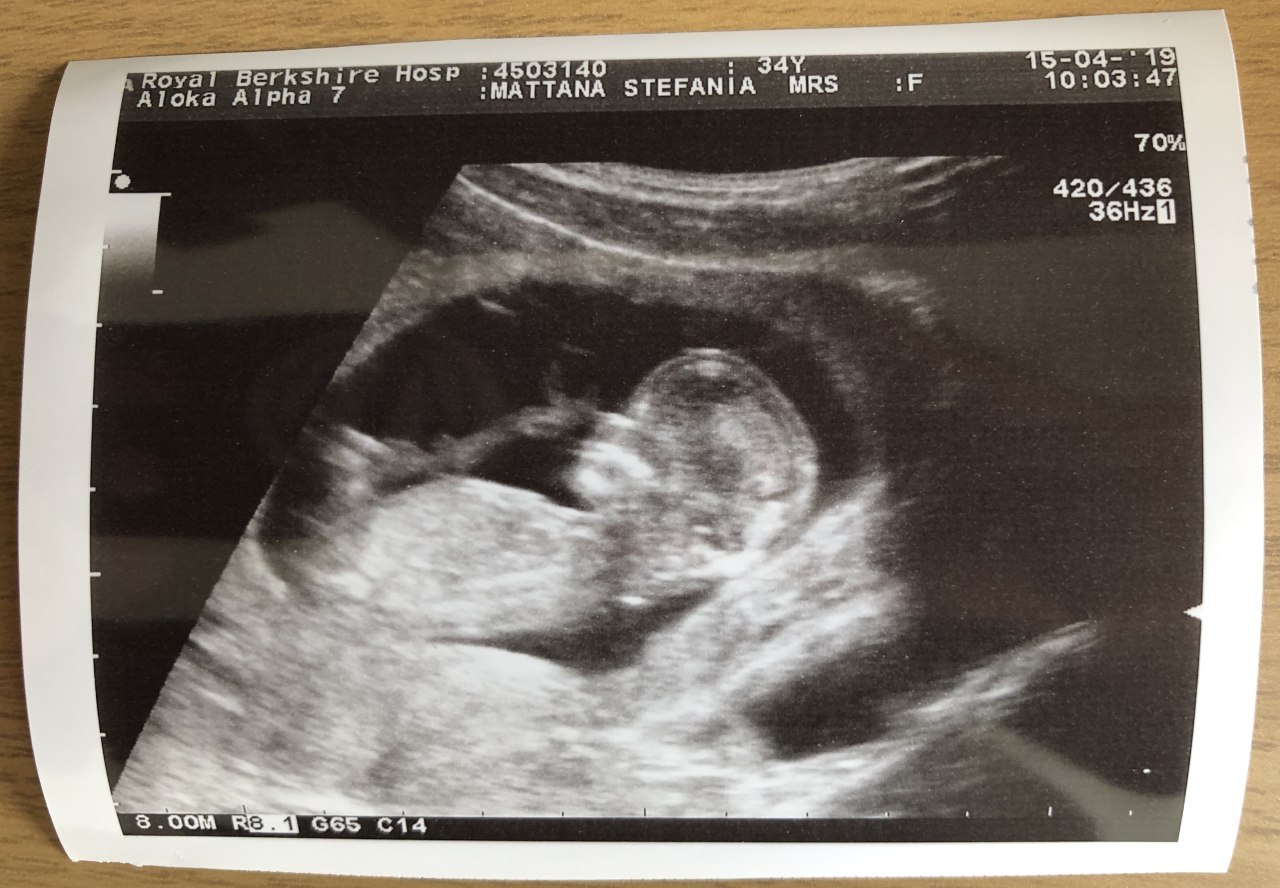

Weeks 12-13: check-in scan and announcements

On Monday Apr 15th we went to the Maternity block at Royal Berkshire Hospital to run the screening scan to check on Frosty.

The scan aimed mainly to take the nuchal translucency measurements, that will be cross-checked with my blood values to have some info about the chances of Frosty contracting Down’s, Pateau’s and/or Edward’s Syndromes.

We didn’t focus on that, but on seeing how Frosty’s doing in the oven.

Here they are, in a classic facepalm pose:

Frosty is such an athlete already: they didn’t stay still one minute! They kept rolling, doing hip thrusts and stretching their back. It was amazing to see how lively they are. If the apple doesn’t fall far from the tree, we should start sorting out a home gym ASAP, not a nursery.